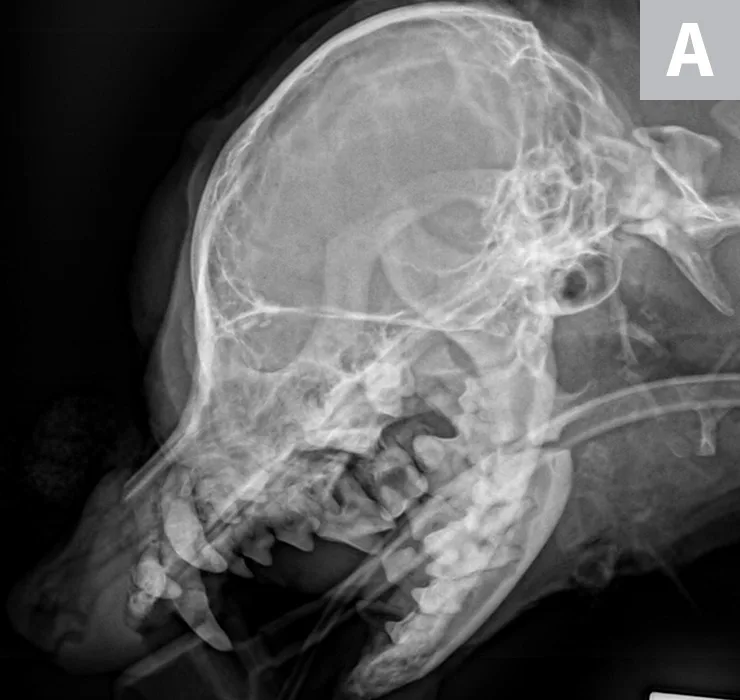

Lateral skull x-ray of dog with endotracheal tube in place and radiopaque cerclage wire around base of mandibular canines.

Lateral radiograph showing placement of a mandibular symphyseal wire in a dog